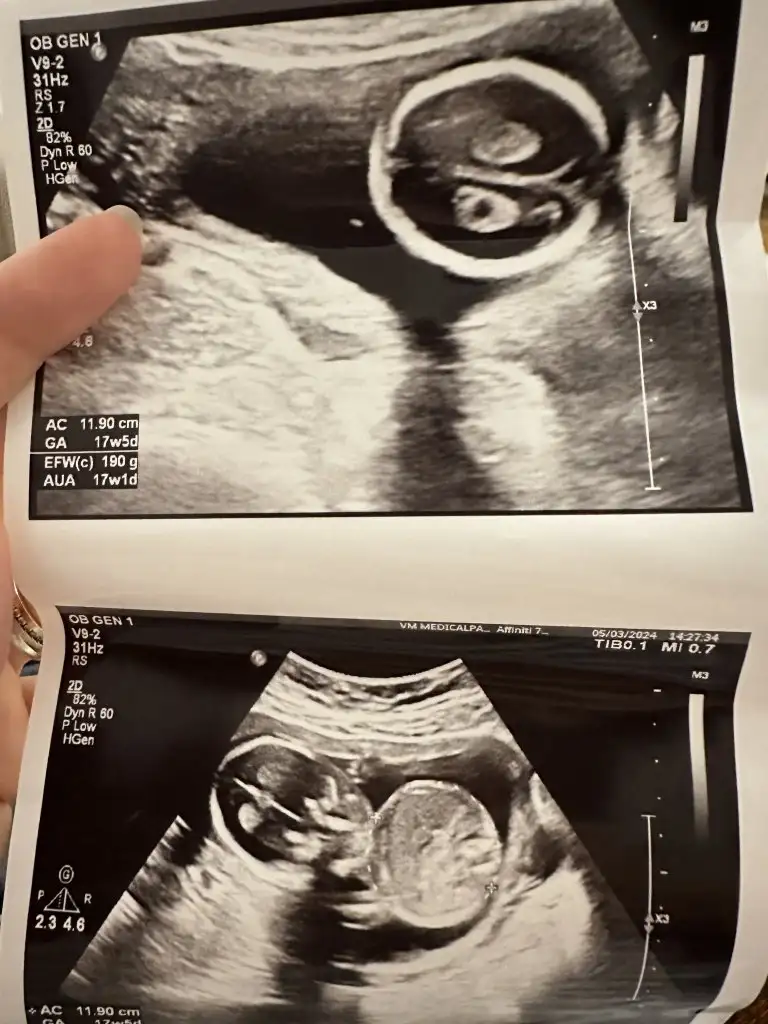

17 haftalık dedi bana ben zaten sordum ona cinsiyet bellimi diye dedi bakıyorum dedi bana o bakarken bız baya doktorla konuştuk hikayemi anlatim ona oda baktı kalktım.sordum.oyle dedi17 haftalık yanılma ihtimali çok az canım. Ben daha11 haftalıkken öğrenmiştim erkek çocuklarımı mesela ikisini de. Yanılmamışlardı. Ultrasonda hızlıca baktıysa belki yanılma ihtimali olabilir ama devlette cinsiyet i geç söylerler yanılma olmaması için

Ay yeter artık net baksınlar şu bacak arasına bebisin niye çevirmiyolar ultrason aletini Bi iki çevirince bacak arasına denk geliyor zaten 17 haftada benziyor demeleri saçma artık ben bile çatlicam senin bebisin cinsiyeti ne acaba diye seni dusunemiyorum17 haftalık dedi bana ben zaten sordum ona cinsiyet bellimi diye dedi bakıyorum dedi bana o bakarken bız baya doktorla konuştuk hikayemi anlatim ona oda baktı kalktım.sordum.oyle dedi

Aynen ben catlicam artık ya direk diyecem zaten ya ne kadar zor cinsiyet kesin budur demesiAy yeter artık net baksınlar şu bacak arasına bebisin niye çevirmiyolar ultrason aletini Bi iki çevirince bacak arasına denk geliyor zaten 17 haftada benziyor demeleri saçma artık ben bile çatlicam senin bebisin cinsiyeti ne acaba diye seni dusunemiyorumyarın direk cinsiyet için geldim de konuyu değiştirmeden direk baksın Dr